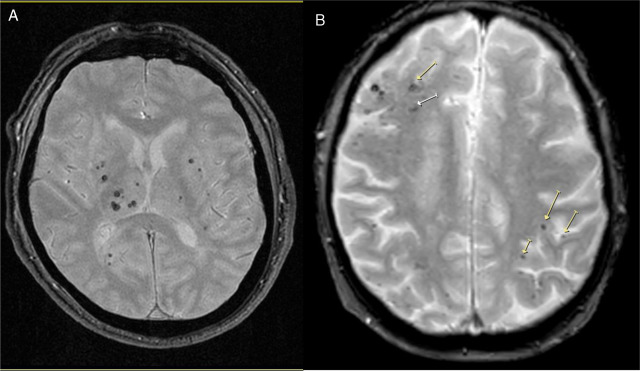

Enfermedad de los vasos cerebrales pequeños en la mediana edad y función cognitiva en etapas posteriores de la vida

La presencia de enfermedad de vasos cerebrales pequeños en la resonancia magnética de adultos asintomáticos se asoció de manera independiente con un deterioro del funcionamiento ejecutivo durante un período de seguimiento de 8 años en esta población general coreana de edad mediana a avanzada. The Lancet Regional Health Western Pacific, febrero de 2025.